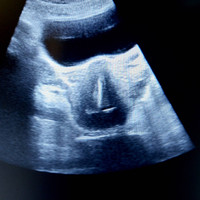

Kebobolan Hamil, Ternyata IUD Ibu Ini Patah dan Hilang, Kok Bisa Ya?